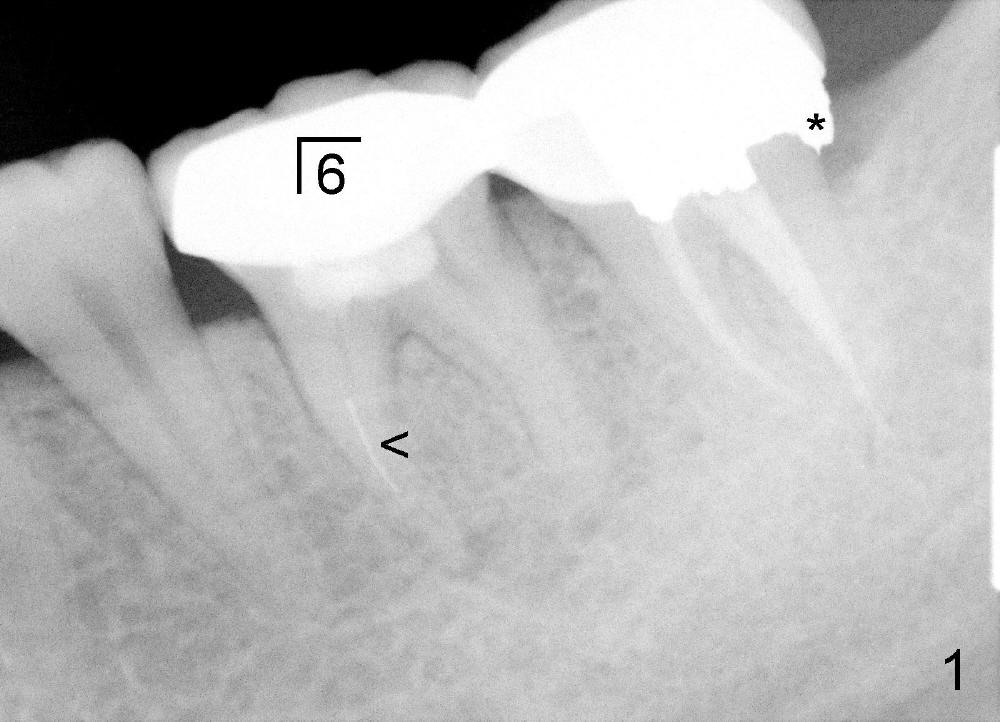

二十九岁辛小姐张口时左下颌骨疼痛要求治疗,出国前左下第一磨牙杀神经(图一),近中有断针(箭头),牙齿有扣痛,我们建议专科诊治,但是她不肯去。只好打肿脸孔充胖子,似乎从来没有处理过别人造成的断针,不知断针在颊侧还是舌侧。事先讨论过各种并发症,特别是TMD,根管治疗重做时间长,可能加重TMD,病人仿佛理解。心想最坏拔除植牙。

第一第二磨牙牙冠连在一起(图一;*:第二磨牙牙冠远中边缘坐在银汞充填物上),首先除去第一磨牙牙冠和冠髓腔松软充填物,后者有若干年久违丁香油气味,很容易找到远中颊舌侧(DB, DL)根管口,扩大也没什么问题(直到30/.06)。扩大针容易插入近中颊侧根管(MB),但是根尖三分之一有些阻塞,近中舌侧根管(ML)冠三分之一就阻塞,说明断针在舌侧根管,用Piezo超声波和diamond tip扩大近中舌侧根管口,也使用二号Gates-Glidden,然后使用C6, 8 扩大针慢慢地通过断针(bypass),最困难却是根尖三分之一阻塞部分(颊舌侧,尤其是舌侧),可能是断针原因。